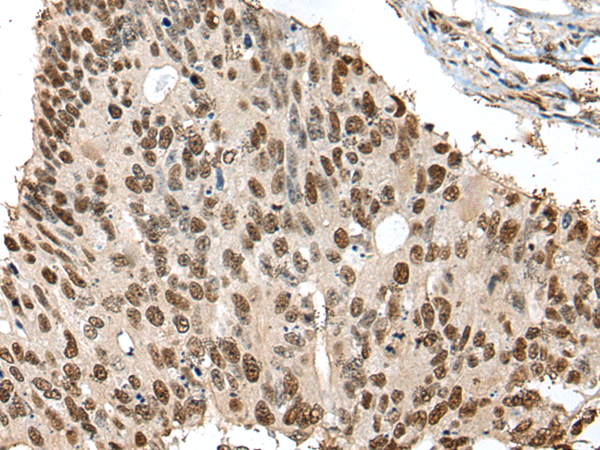

The image is immunohistochemistry of paraffin-embedded Human colorectal cancer tissue using (UBR7 Antibody) at dilution 1/30. (Original magnification: ×200)